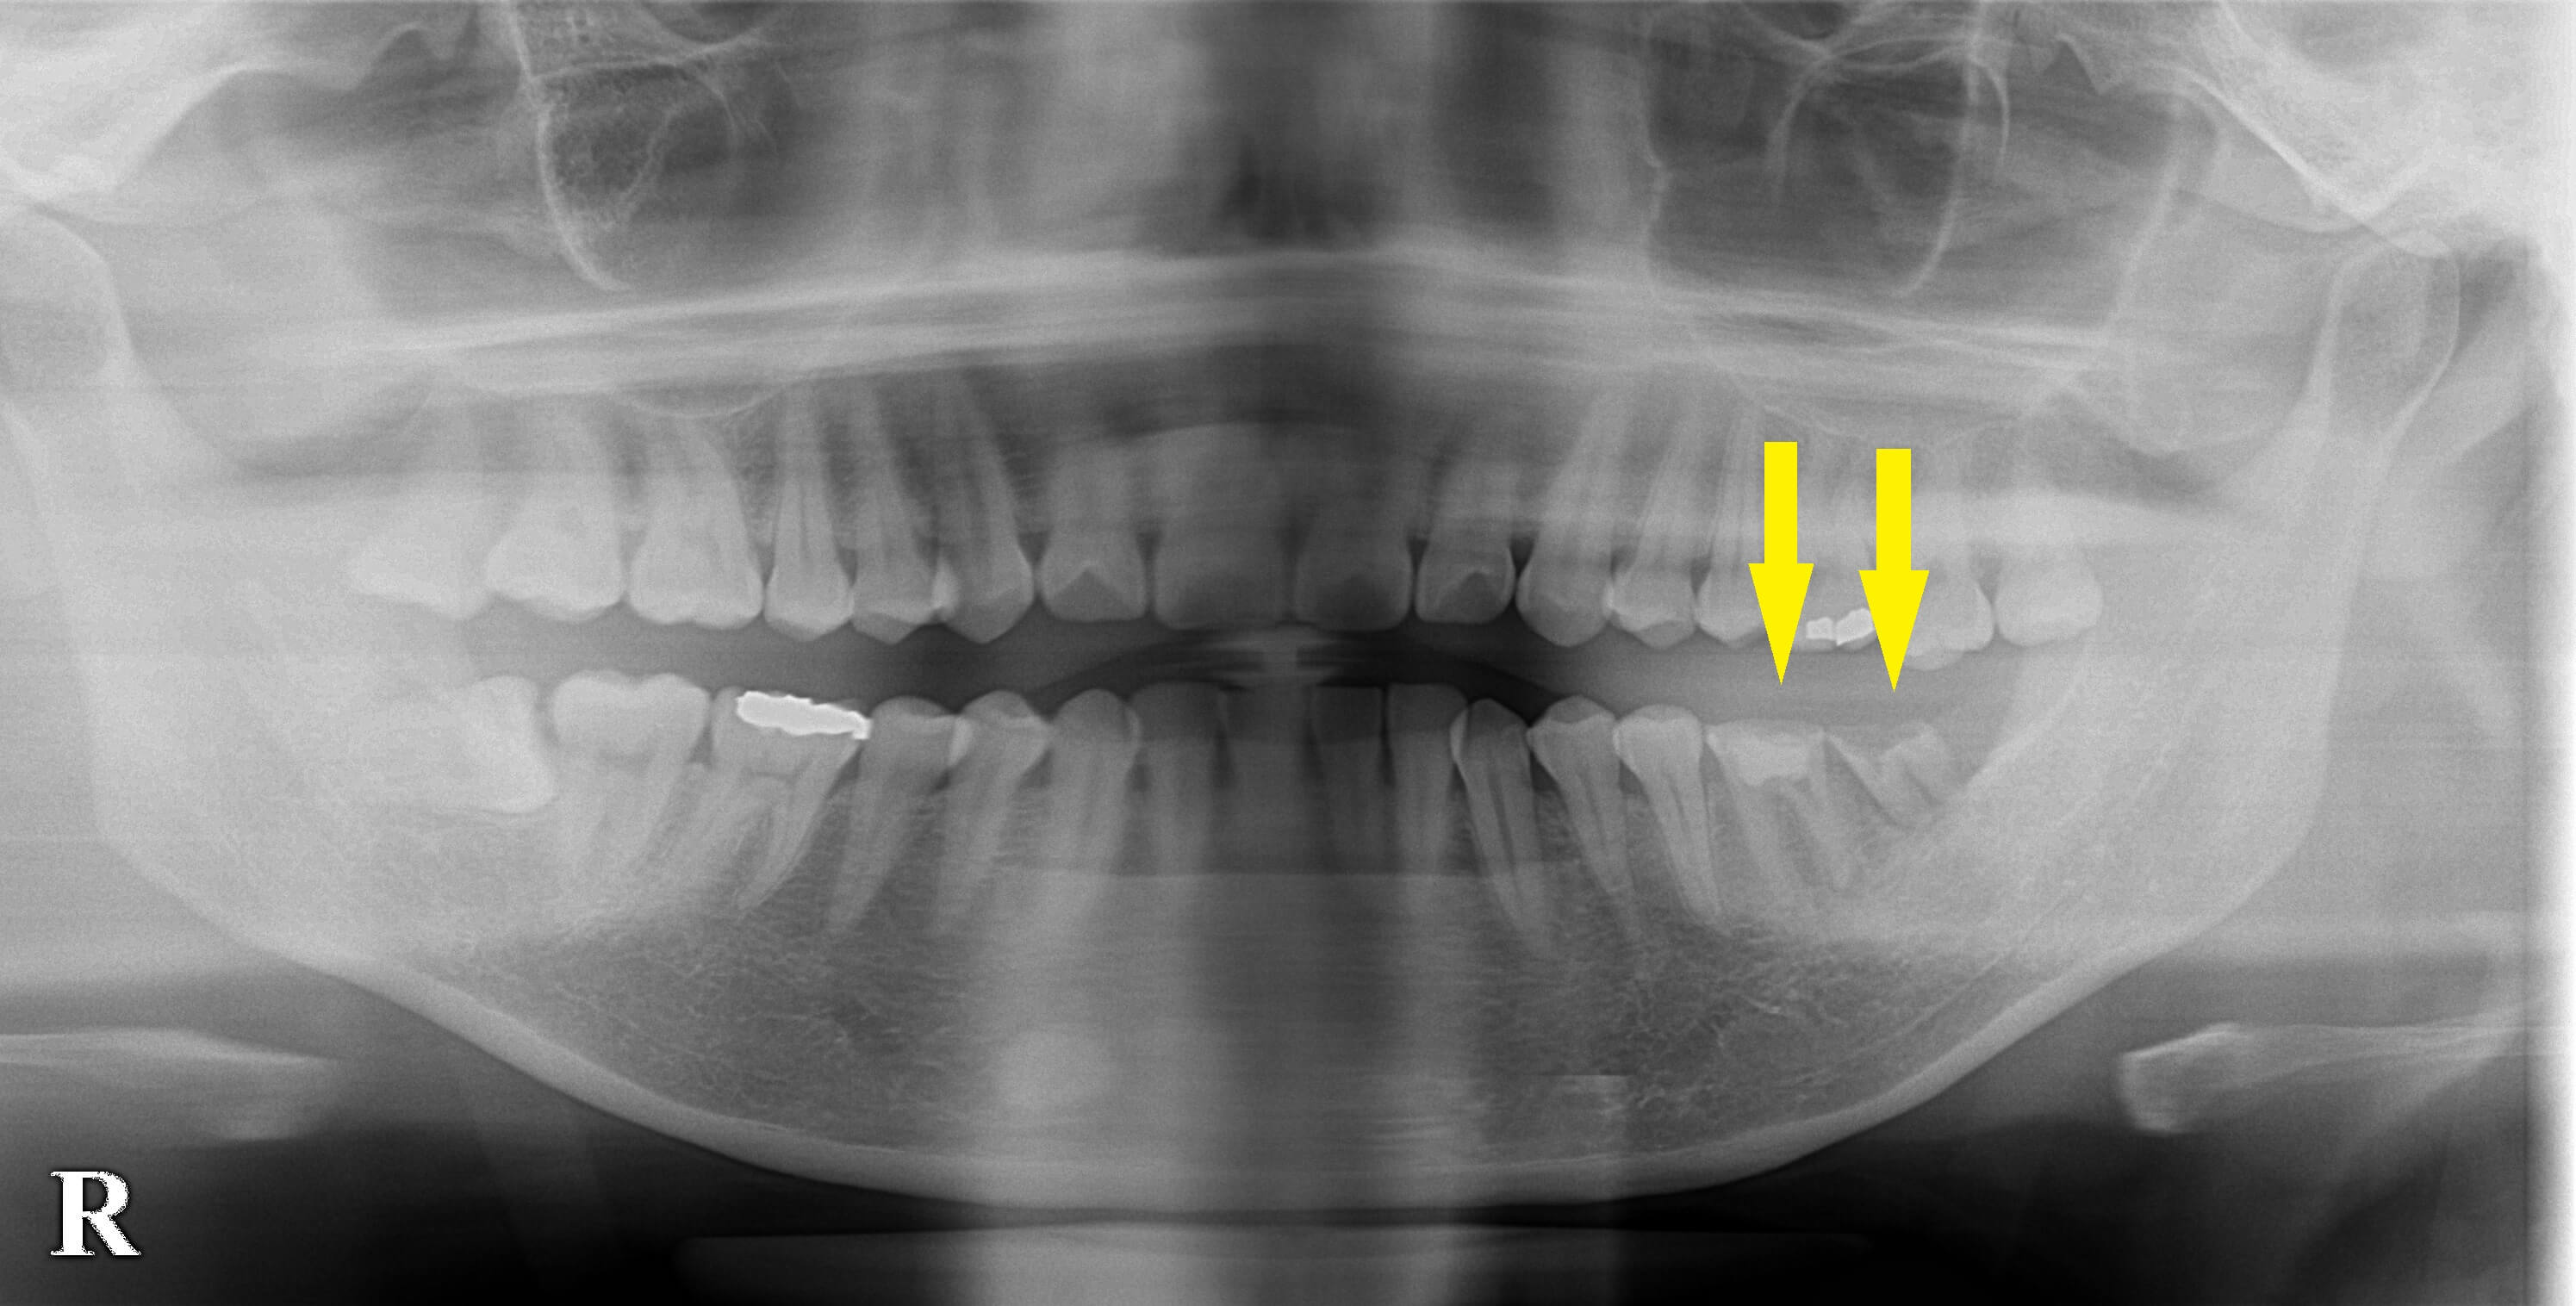

左下顎大臼歯2本が、数年前から痛みと腫れを繰り返し、何度も歯根の治療をされているそうですが、

結局症状が取れず、抜歯を覚悟したそうです。

数か月治癒を待って、本日同部に、2本のインプラント埋入術を行いました。